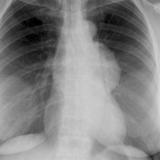

Case 8a Thymoma PA

Date: 03/27/2009

Views: 9452